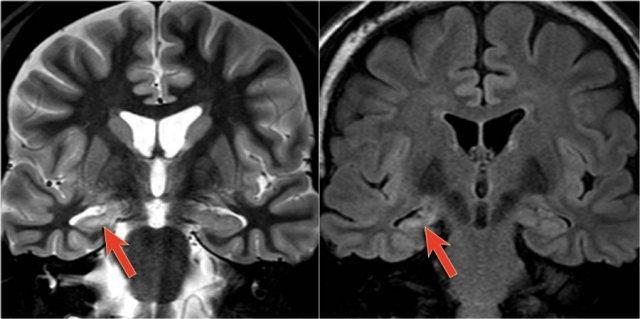

Các hình ảnh cho thấy loạn sản vỏ não khu trú điển hình.

Có hình ảnh dày vỏ não và mờ ranh giới chất xám/chất trắng trên chuỗi xung T1W (bên trái).

Ảnh FLAIR bên phải cho thấy tăng tín hiệu vùng dưới vỏ.

Các hình ảnh cho thấy bất thường tín hiệu vỏ não và dưới vỏ trên chuỗi xung T2W và FLAIR ở thùy thái dương trái, phù hợp với loạn sản vỏ não khu trú.

Lưu ý hình ảnh hồi hải mã tăng tín hiệu T2/FLAIR kèm teo nhỏ là hậu quả của xơ cứng thùy thái dương giữa, tức là bệnh lý kép.